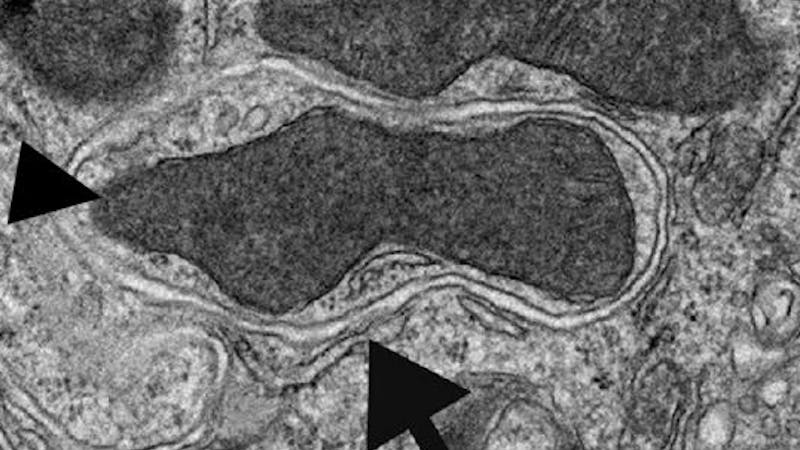

Cuando las células ayunan, reutilizan parte de sus componentes “basura” para tratar de darles un nuevo uso. Este proceso de autofagia, esencial para sobrevivir, puede ayudar también a enfrentar enfermedades.